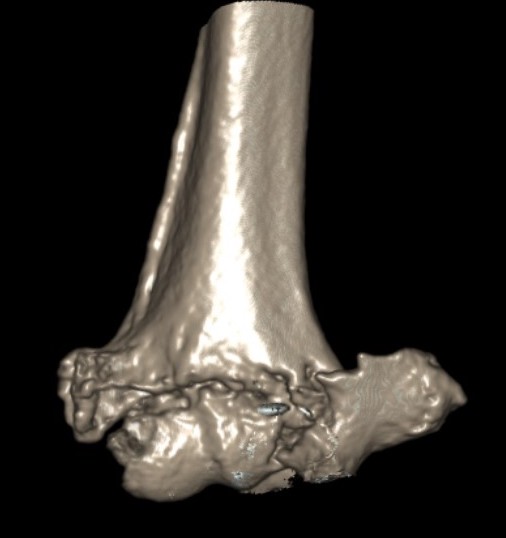

Type C: Complete articular fractures

CT scan